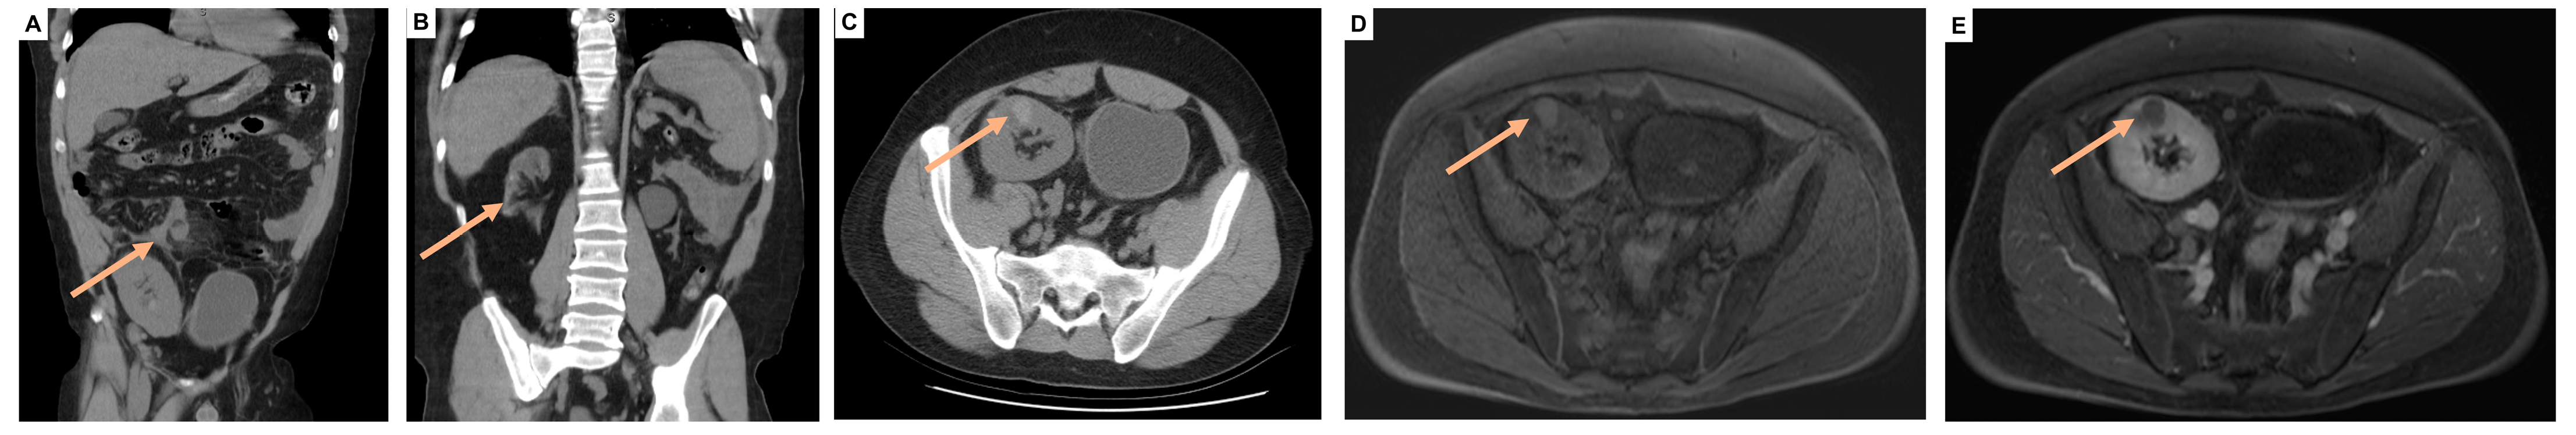

2.2. Diagnostic Imaging